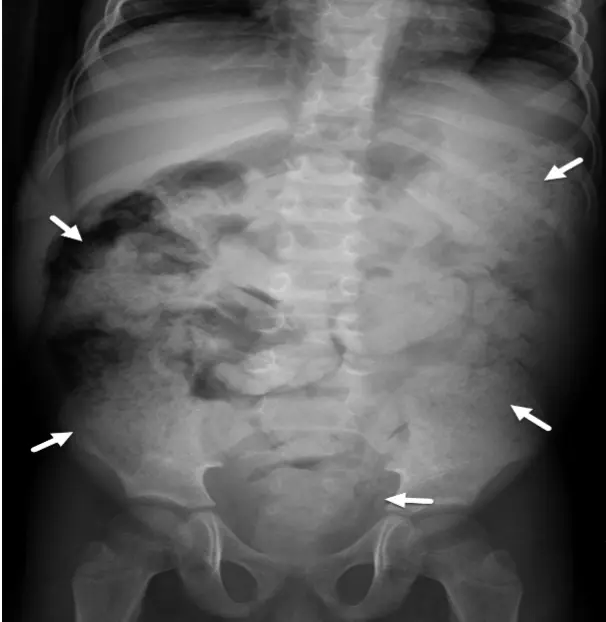

Abdominal X-ray and water soluble contrast enema shows large amount of stool in the colon. Stool may appear as mottled or glandular densities due to gas mixed with feces. Also it shows gas in the intestine and sometimes shows air fluid levels if there is obstruction.